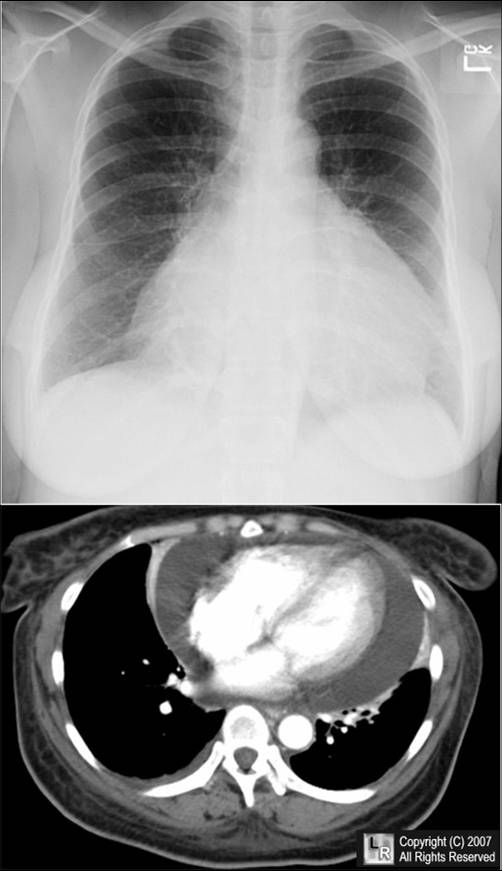

weekly clinical round for undergraduate from 8 to 11 AM during which interpretation of CHEST X rays was done for all cases of cardiothoracic surgery, gived by 2 staf member for 3 months